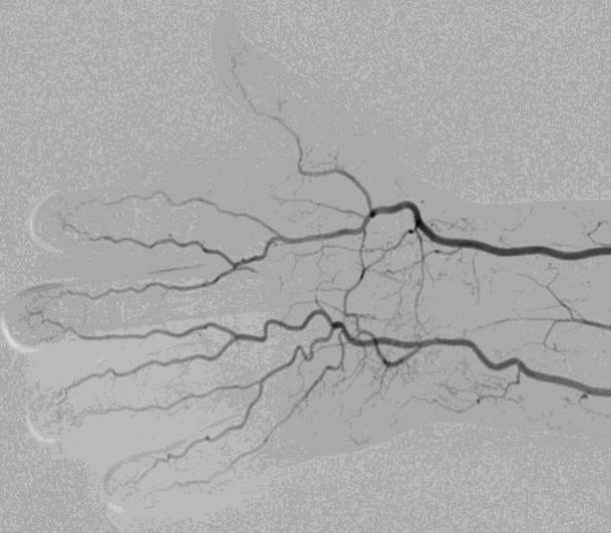

手部动脉解剖

• 手部的桡动脉和尺动脉通过四个弓相互吻合

• 弓的解剖结构存在显著变异

• 完整的浅掌弓和深掌弓应能耐受桡动脉结扎/闭塞

• 不完整的弓解剖结构会增加后续指端缺血的风险

• 多数研究报道,超过80%的患者存在完整的浅掌弓,超过90%的患者存在完整的深掌弓